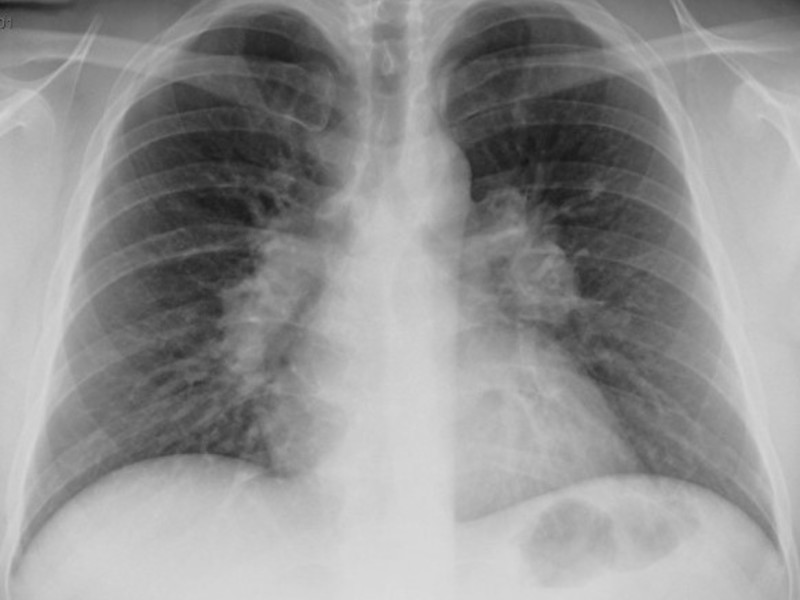

Первый признак пневмонии на рентгеновском снимке – появление очагов затемнения с неровными контурами в разных частях легкого, которые могут иметь разный размер, от 3-4-х до 12 мм.

Тени различают по внешнему виду (круглые, овальные кольцевидные) и интенсивности окраски – чем темнее пятно, тем сильнее выражен патологический процесс.

При поражении лимфатических узлов и нарушении кровоснабжения органа могут наблюдаться изменения корней легких, а если болезнь затронула плевру – нарушение в рисунке куполов диафрагмы. В остальном проявления пневмонии зависят от стадии, формы и клинических особенностей заболевания:

- Крупозная пневмония. Наблюдаются изменения нормального легочного рисунка, жидкость в полости плевры, признаки инфильтрации одной из долей легкого, расширение корней. По мере развития воспалительного процесса выраженность изменений и интенсивность окраски затемнений усиливается.

Признаки воспаления лёгких на снимке называют «затемнениями», отображаются они белым цветом, поскольку само изображение является негативом.

Пневмония на снимке, в частности затемнения, характеризуются следующим образом:

- Распространённые. Визуализируют в пределах одного сегмента.

- Субтотальные. Затемнение большей части поля органа или нескольких сегментов.

- Тотальные. Патологический процесс охватывает всю область лёгочной ткани. Сильная пневмония слева